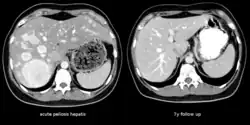

| The CT scan of a patient with peliosis hepatis (left): The follow-up CT (right) after 7 years shows full remission. | |